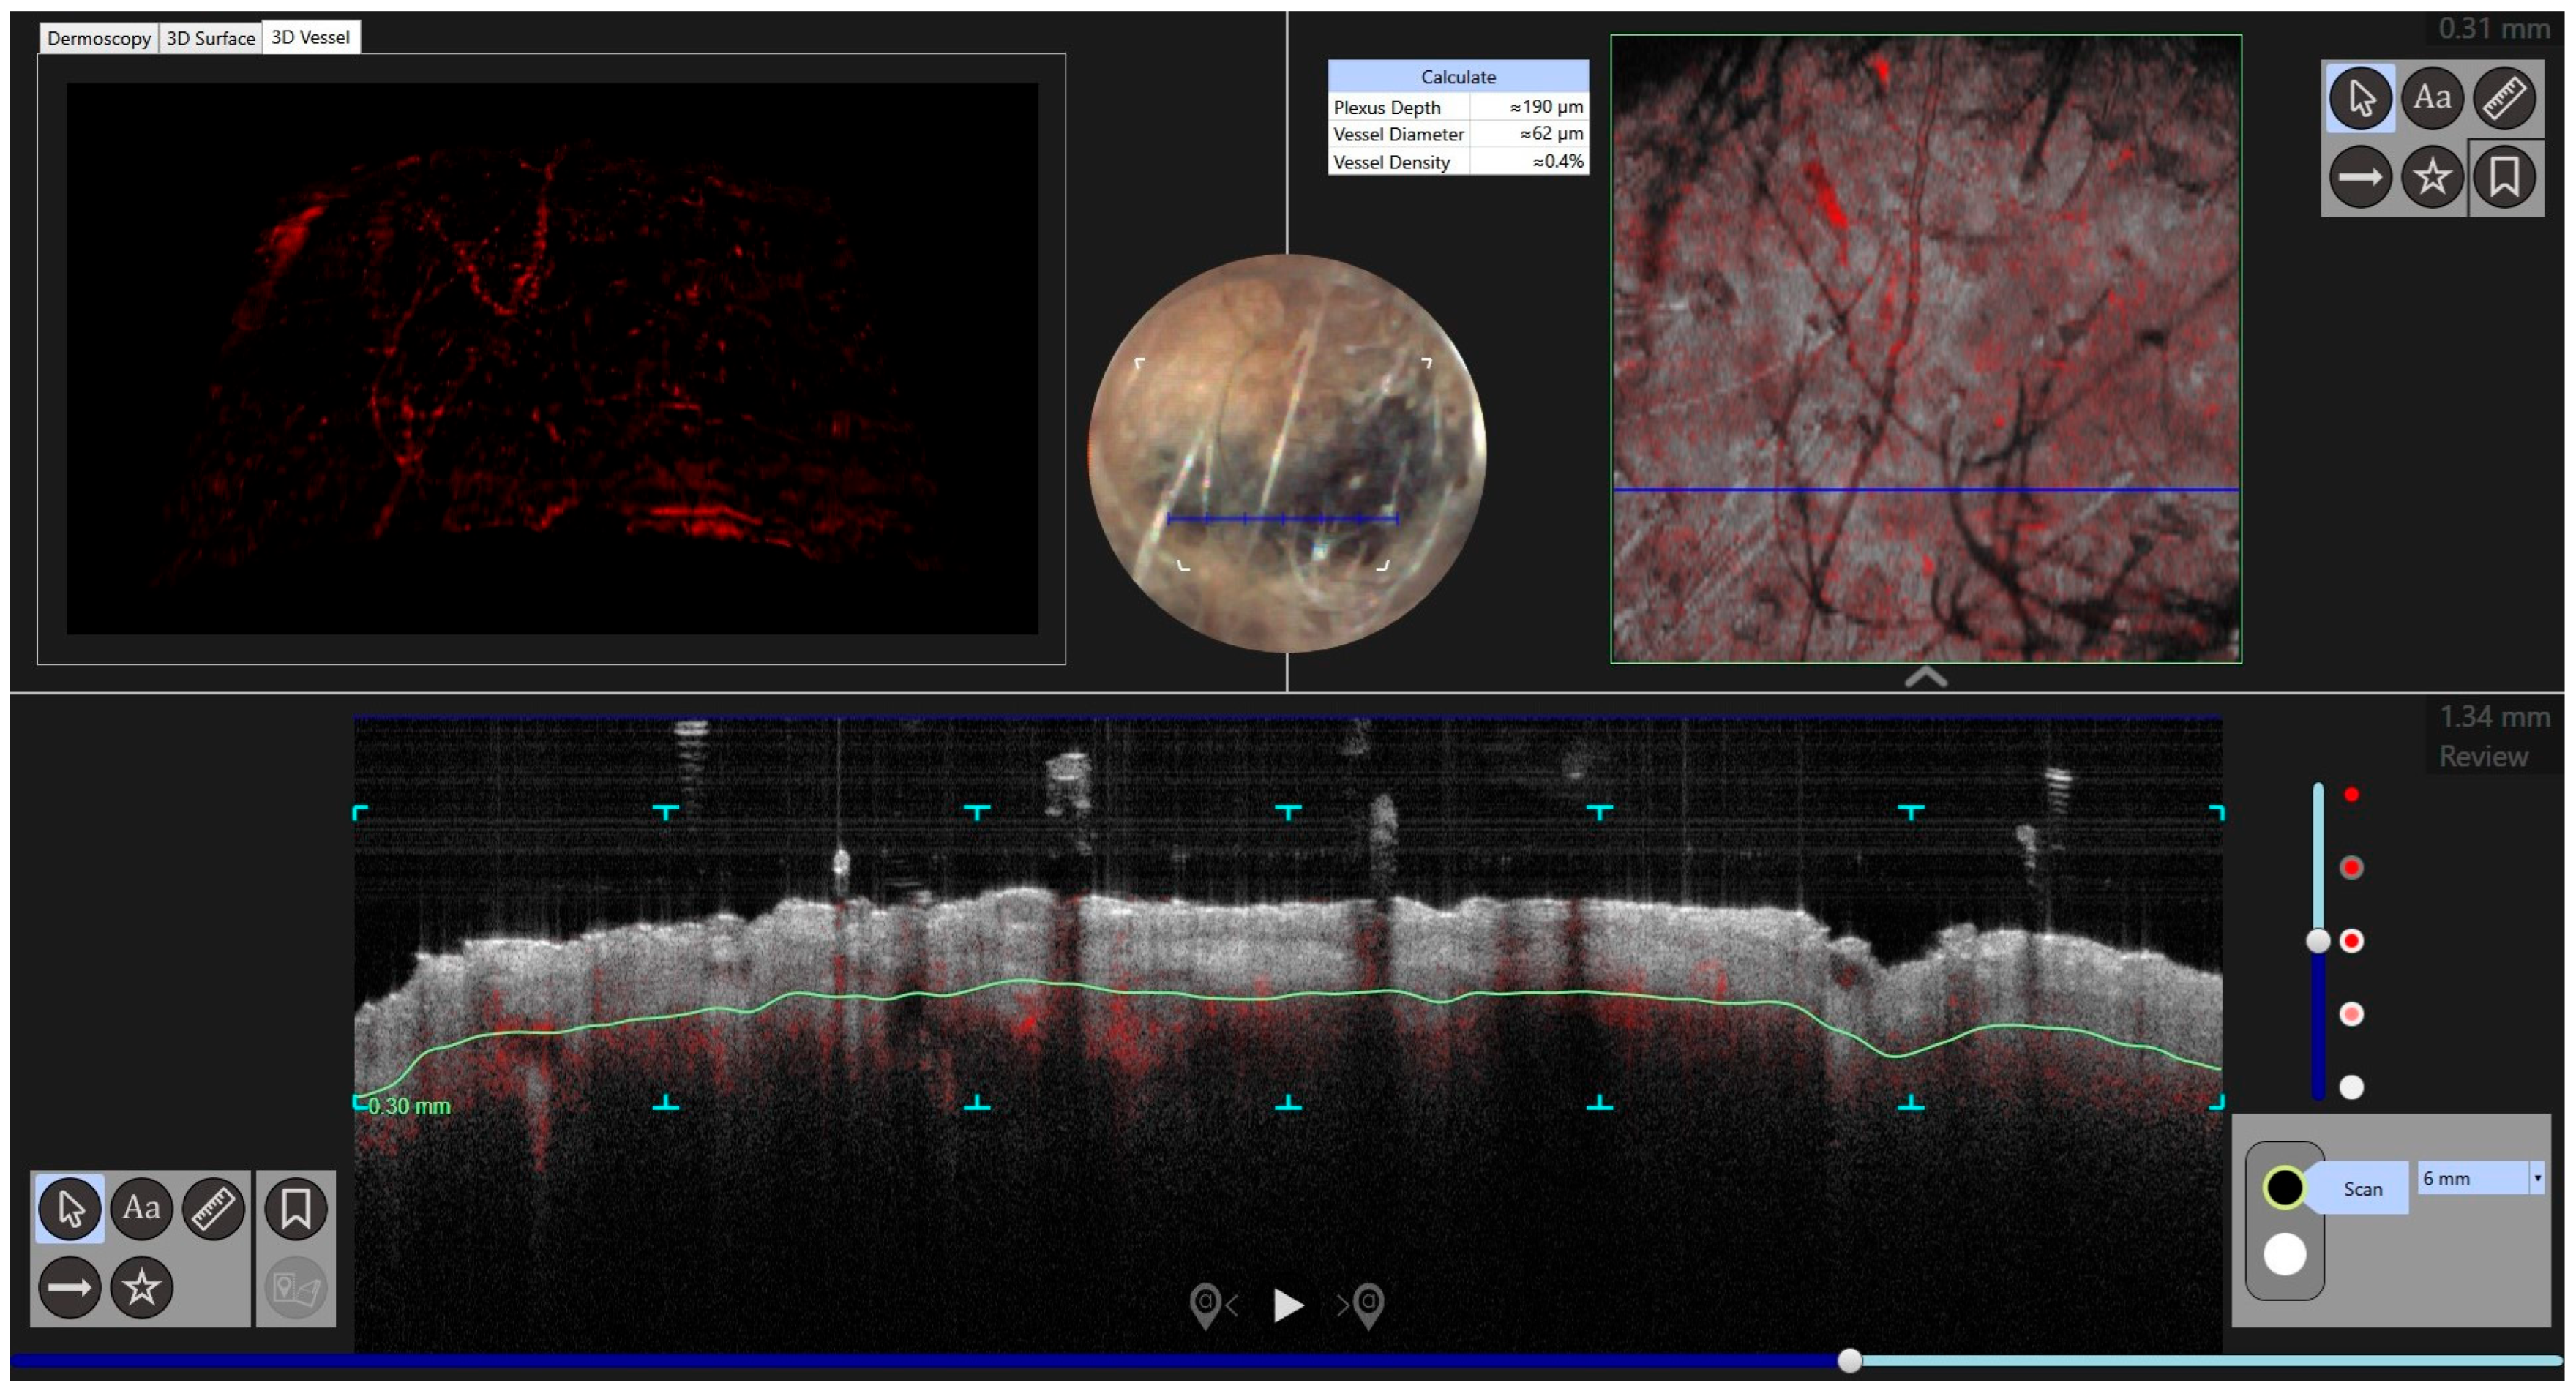

- Del Río-Sancho, S.; Gallay, C.; Ventéjou, S.; Christen-Zaech, S. Non-invasive imaging of agminated Spitz nevi with line-field confocal optical coherence tomography. J. Eur. Acad. Dermatol. Venereol. 2023, 37, e658–e659. [Google Scholar] [CrossRef]